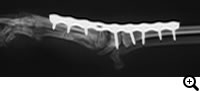

レントゲン検査など

治療

外科適応の場合は全関節固定術、部分関節固定術、スーチャーアンカー法などをおこない、手根関節を固定します